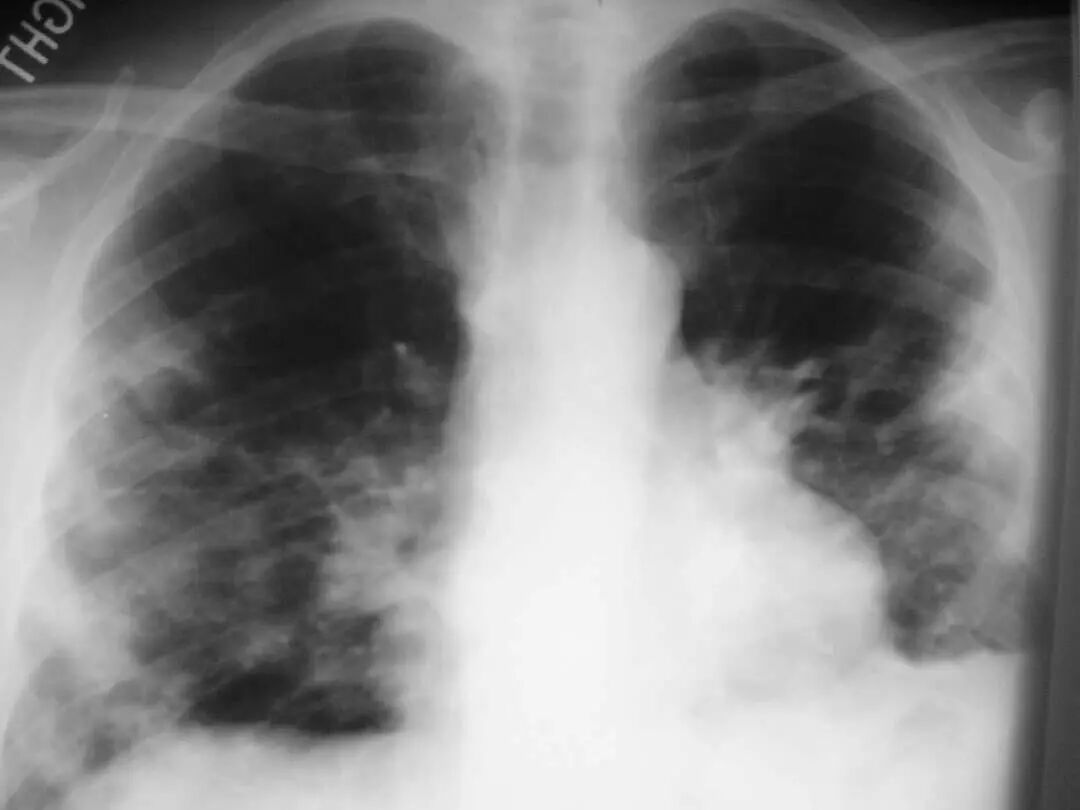

图1.2 细菌性肺炎。双肺下叶肺炎患者影像。